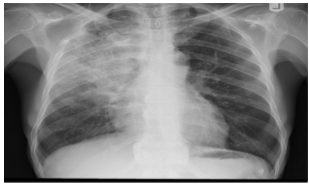

- AP chest film which shows complete opacification of the whole right lung - (1 .with shifted mediastinum and trachea to the left side

- .This indicates pleural effusion (PE) - (2

- After inserting chest tube, pus was coming out. This means that the PE is - (3 .an Empyema

- .The cause of this empyema is most likely a Bacterial Pneumonia - (4

- The age of the patient is 10 years which means that the most likely - (5 .organism is Streptococcus Pneumonae